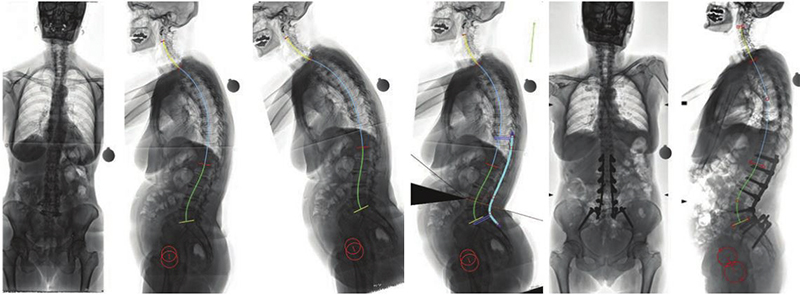

Η αντιμετώπιση των παραμορφώσεων της σπονδυλικής στήλης των ενηλίκων, ένα πολύ ιδιαίτερο και δύσκολο χειρουργικό πρόβλημα, βασίζεται πλέον στον ακριβή, γεωμετρικό, τρισδιάστατο προεγχειρητικό σχεδιασμό, με τη βοήθεια υπολογιστικών προγραμμάτων χειρουργικού σχεδιασμού. Μέσω αυτής της τεχνικής, σχεδιάζεται με απόλυτη ακρίβεια η χειρουργική επέμβαση ενώ παράλληλα προκατασκευάζονται και υπάρχουν διαθέσιμα στο χειρουργείο τα εξατομικευμένα, διαφορετικά για κάθε διαφορετικό ασθενή, υλικά σπονδυλοδεσίας.

Προεγχειρητική εικόνα, εξατομικευμένος υπολογιστικός προεγχειρητικός σχεδιασμός, μετεγχειρητική εικόνα.